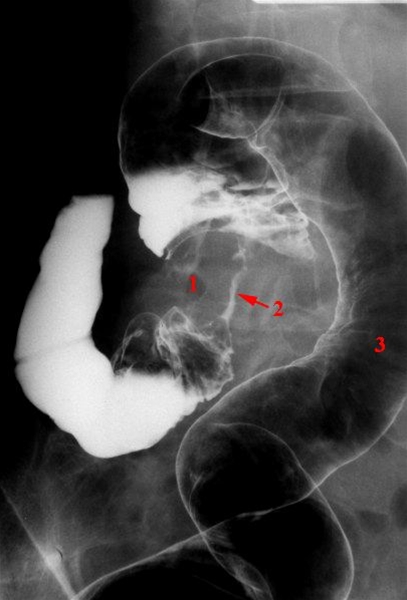

Colon cancer, røntgen

Dobbelt kontrast teknik. I dag bruger man næsten altid CT scanning i stedet for røntgenkontrast undersøgelse

1. Stenoserende tumor i sigmoideum

2. Kontrast i snævert lumen gennem tumor

3. Normal del af sigmoideum